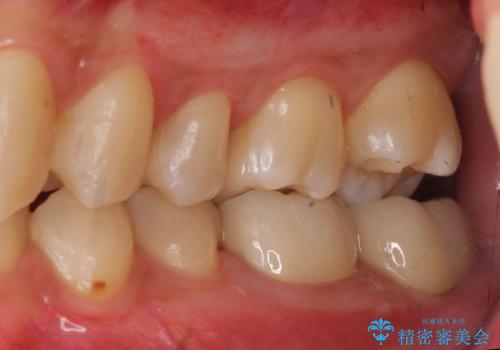

放置した虫歯の治療 親知らずの手前が虫歯

- 詰め物が取れて放置していたとのこと。

虫歯が大きかったため、被せ物(クラウン)としました。

親知らずを抜いてから治療しています。

- 22万円 (左下67 仮歯1万円x2 ジルコニアクラウン10万円x2)費用は治療当時の料金となります

幸い神経を取らずにすみました。